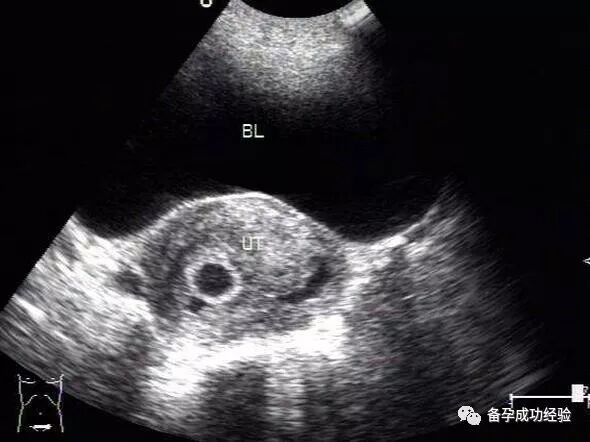

B超检查辐射大吗?

很多朋友因为备孕需要检测排卵或者是做一些检查,接触B超检查的次数相对较多,也因此会很担心,B超检查辐射大吗?相对来讲B超检查的辐射是非常小的,即便是对于孕期的孕妈妈来说,也都是安全的检查手段的。所以,B超检查的问题不必担心,反而B超检查对于备孕、怀孕的各项情况能够比较直观的展现,所以是临床比较便捷的检查手段的。